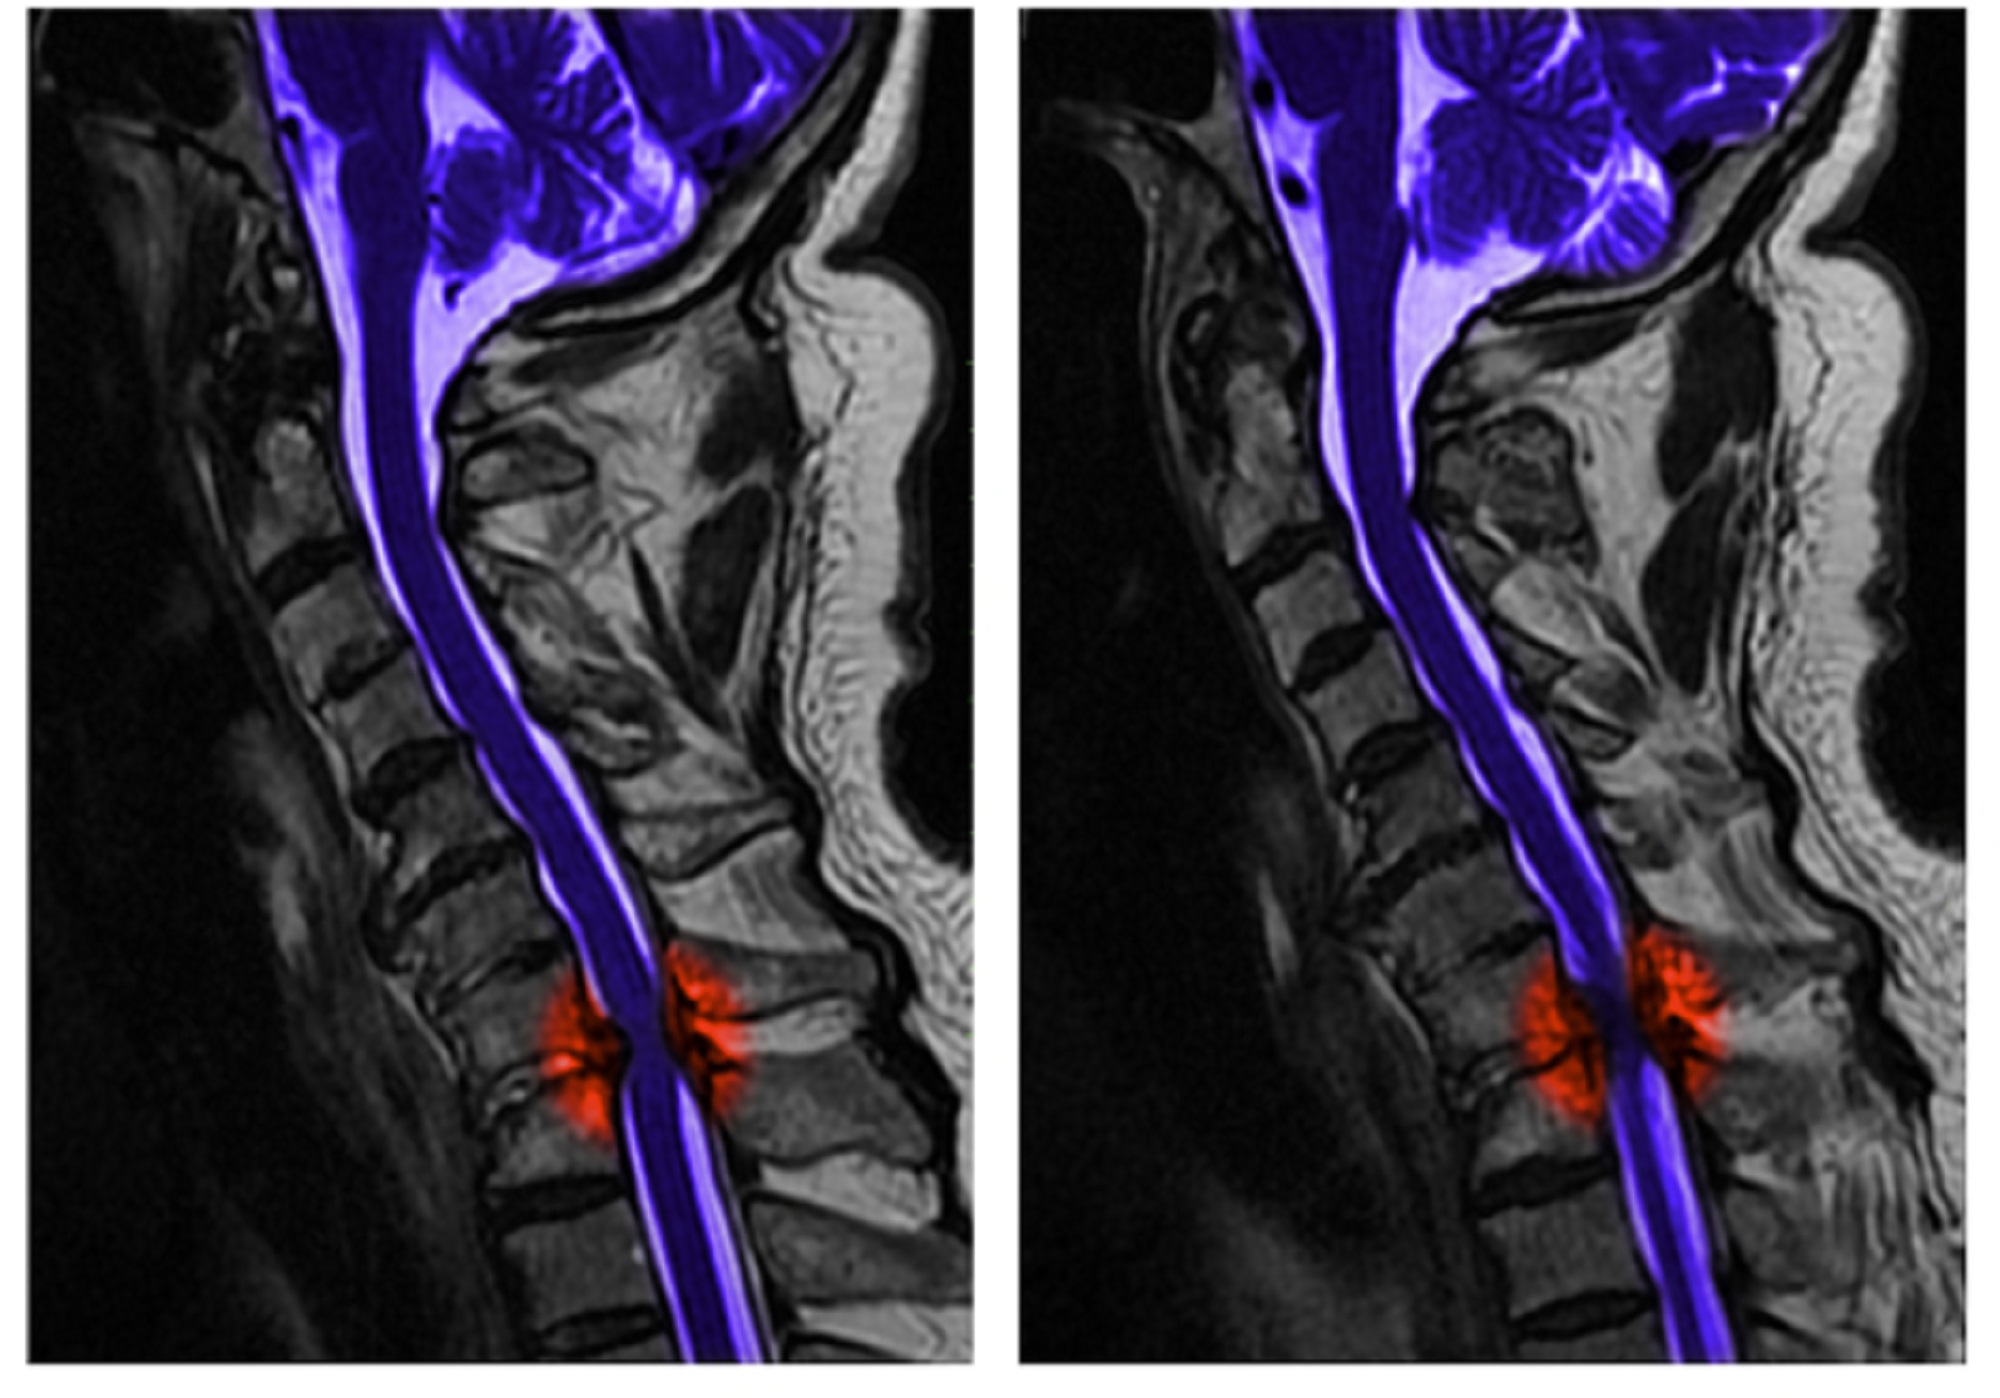

Imaging of spinal cord injury

MRI images of the cervical spine of a 65 year old man who sustained neck trauma and presented to the emergency room withnumbness and tingling of his legs, the result of spinal cor d compression (red) at the level of the disk between the seventh cervical and the first thoracic vertebrae. The brain and spinal cord are shown in purple.